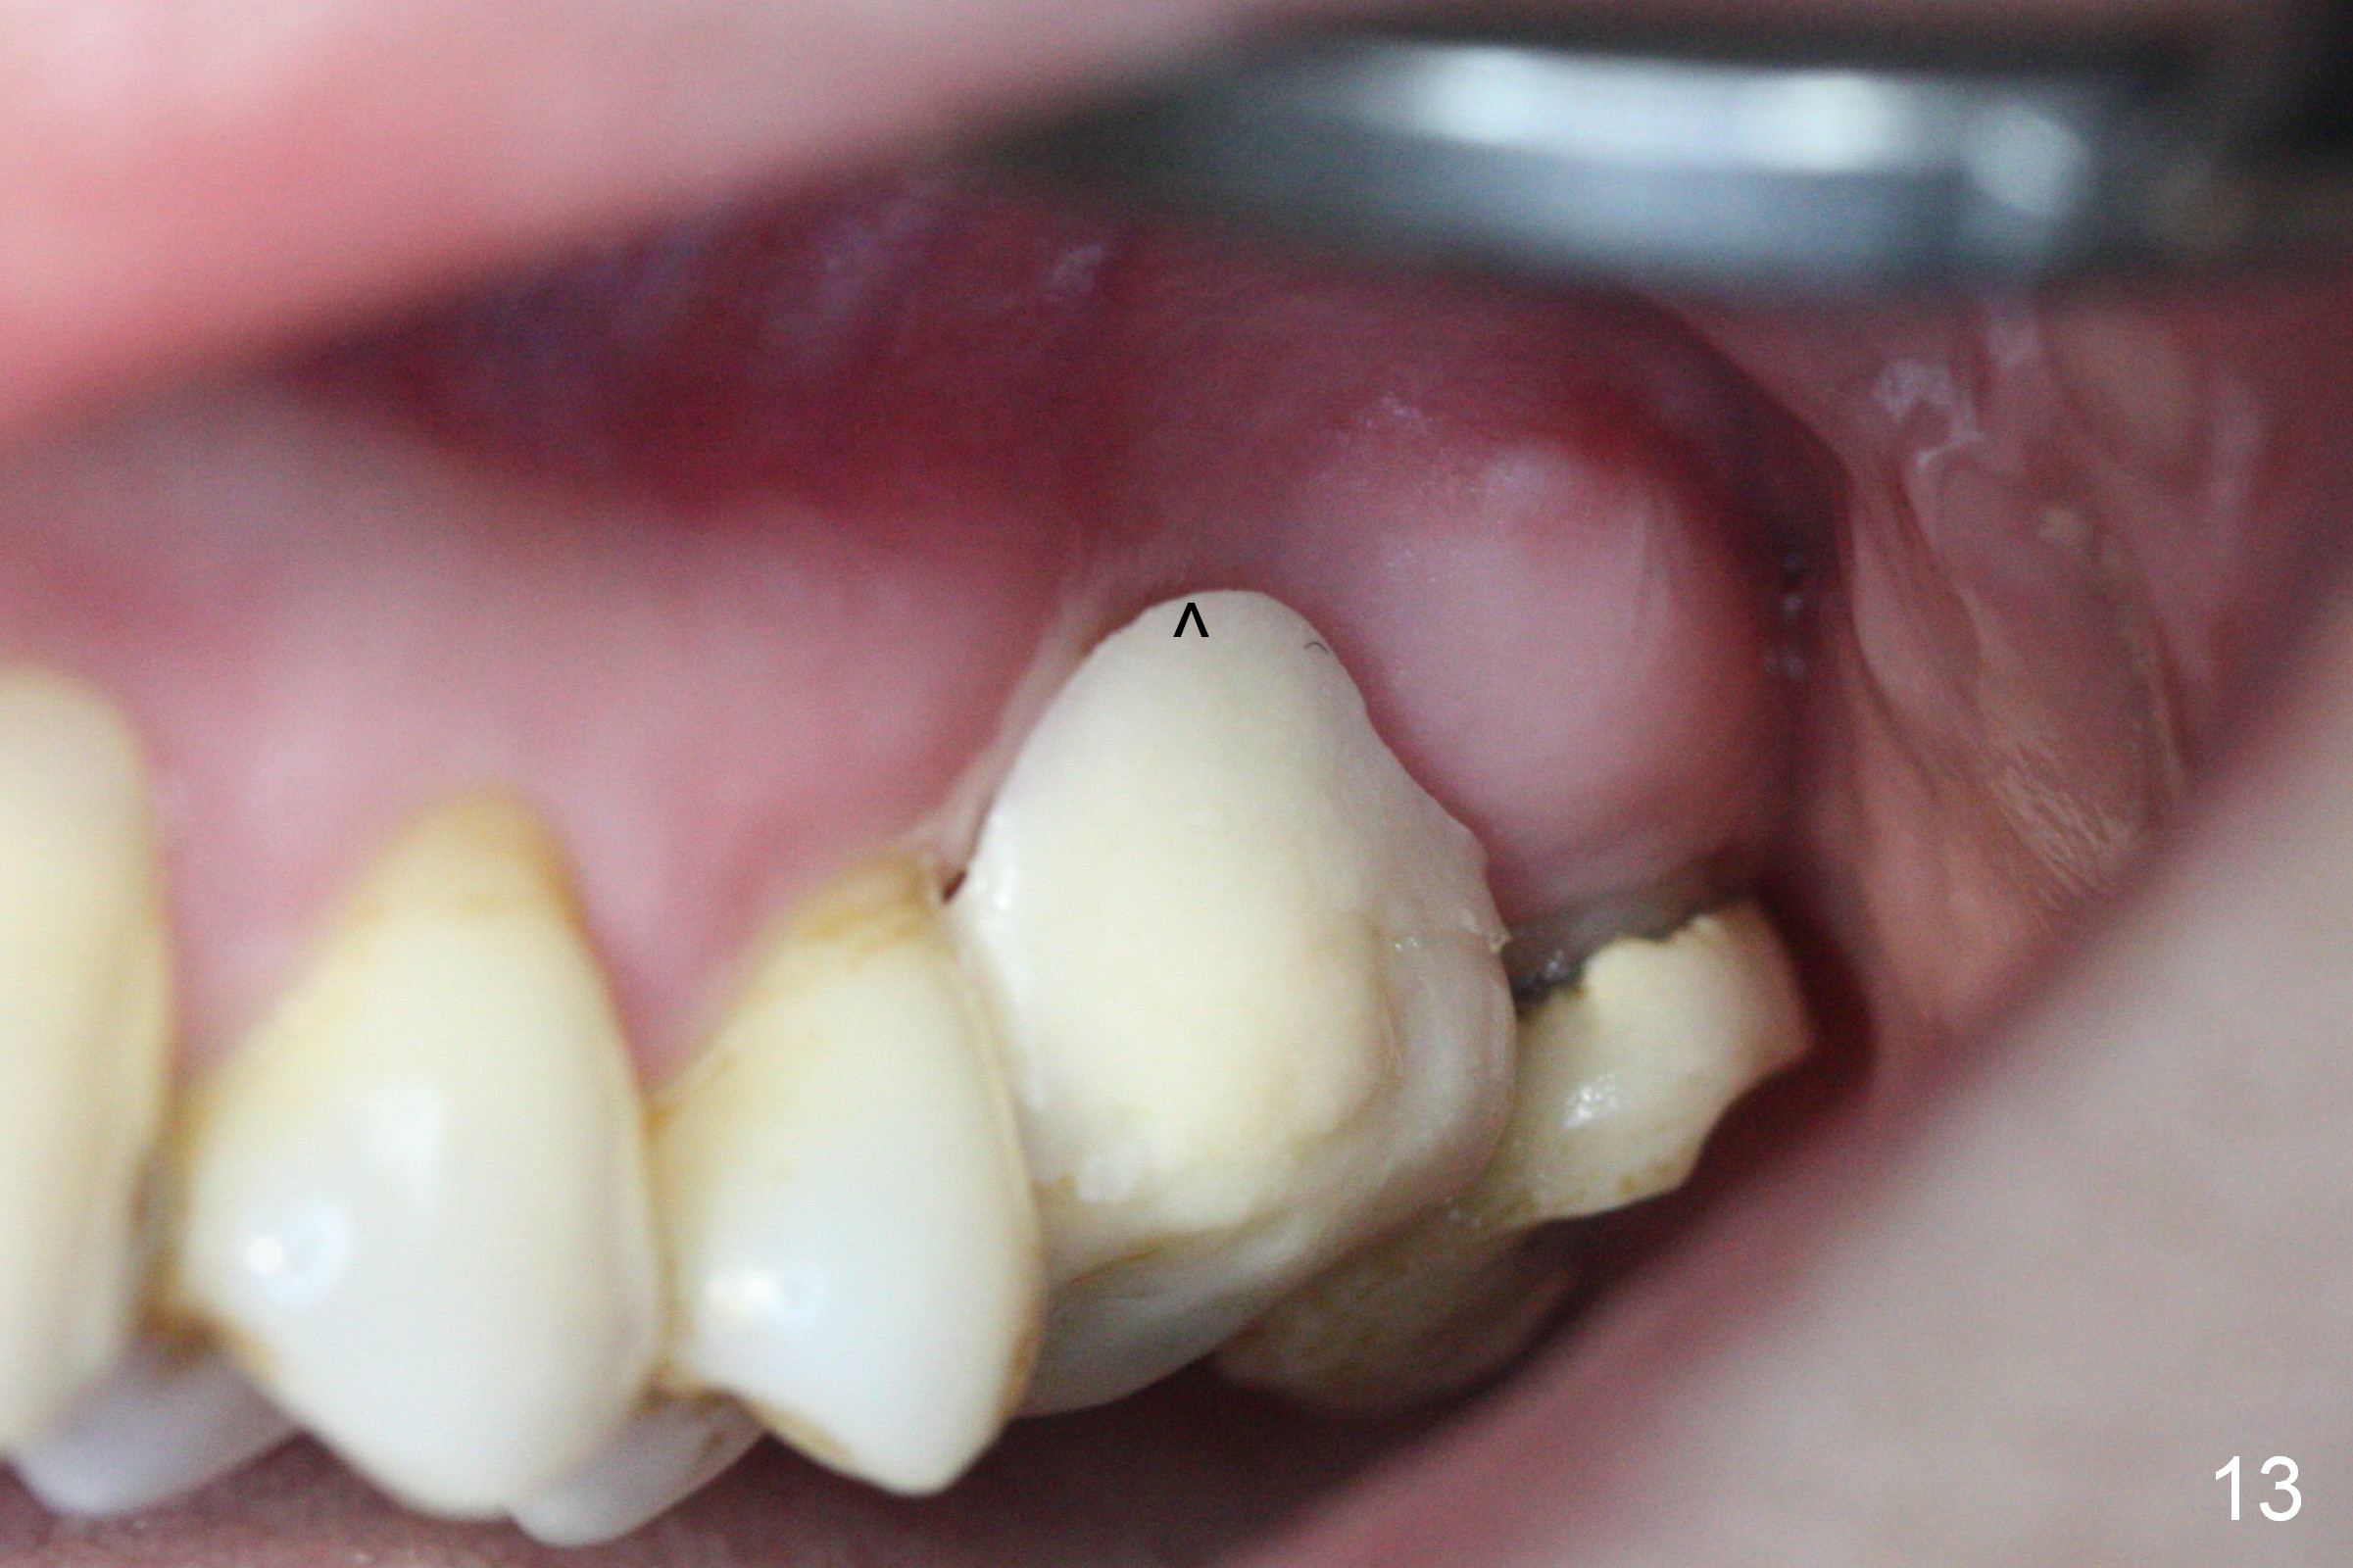

There is abundant subgingival calculus on the surfaces of the extracted tooth at #14 (Fig.1: P: palatal; MB: mesiobuccal), corresponding to the large empty socket (Fig.2 without septal bone, the buccal plate being low). Osteotomy is established palatally with Magic Expander (ME) 3.0 mm for ~ 3 mm deep (Fig.3,4) with minimal stability so that it moves during X-ray taking (Fig.4). Since the bone is dense, Magic drill 4.3 mm is used after application of ME 3.8 and 4.3 mm to complete sinus lift (Fig.5 (panoramic X-ray)). A 5x11 mm implant is placed with ~ 30 Ncm, followed by insertion of 6.5x4(3) mm Hexa abutment, bone graft and collagen membrane (Fig.6). The latter is kept in placed with an immediate provisional with clearance from the opposing dentition (Fig.7 *). Between the 1st and 3rd weeks postop, the buccal gingiva recedes with loss of bone graft (Fig.8 <) and implant thread exposure (Fig.9 * (A: abutment)). After inducing hemorrhage, allograft is placed (Fig.10 >), followed by collagen dressing (Fig.11 >). The wound closes by adding new acrylic (Fig.12 *). Thirteen days later, food is trapped in the buccal gap (Fig.13 ^). It appears that the provisional does not help wound healing. The provisional and abutment are removed; incorporating bone graft (Fig.14 *) and the implant are exposed. After placing collagen plug against the bone graft and implant, the wound is closed by periodontal dressing.